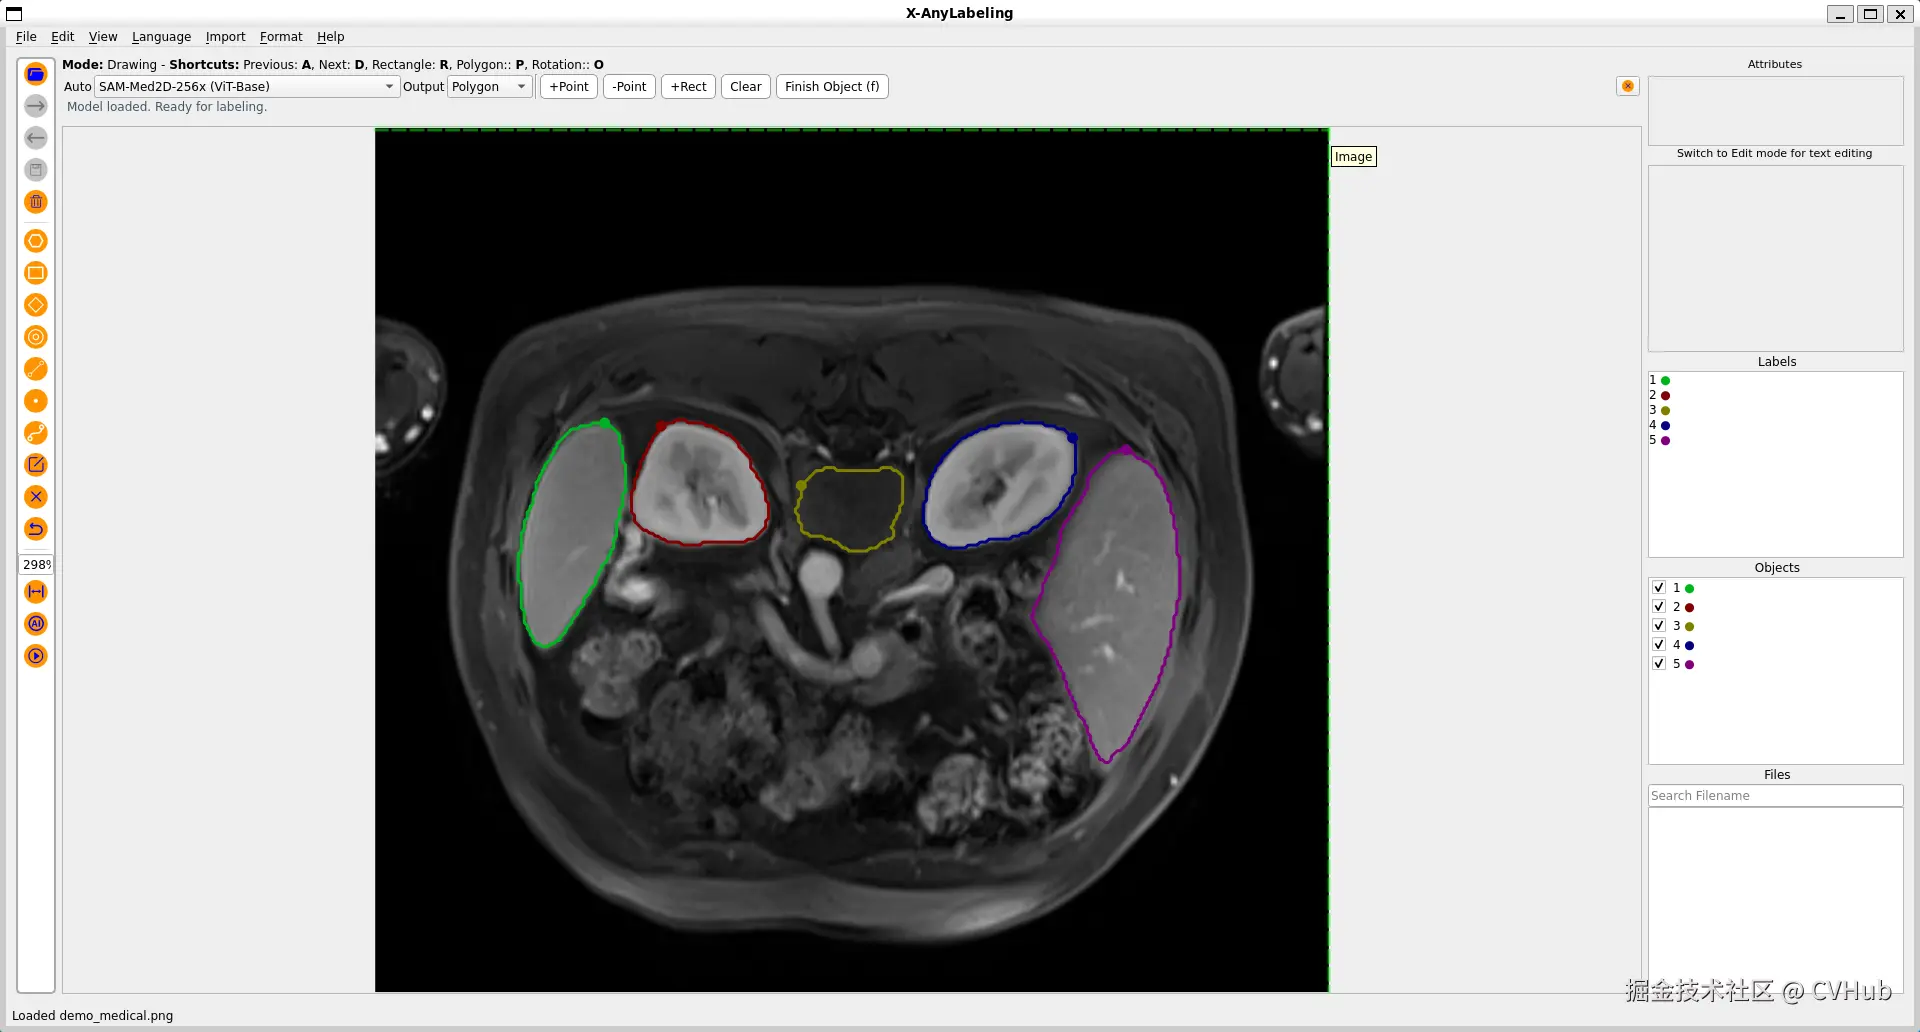

更进一步地,针对医学图像场景,X-AnyLabeling中同样提供了多种基于 SAM 微调的高精度模型,包括:

• SAM-Med2D: 通用医疗图像分割一切模型;

• LVM-Med ISIC SAM:皮肤病灶分割一切模型;

• LVM-Med BUID SAM:超声乳腺癌分割一切模型;

• LVM-Med Kvasir SAM:结直肠息肉分割一切模型;

详情可参考以下链接:

github.com/CVHub520/X-…